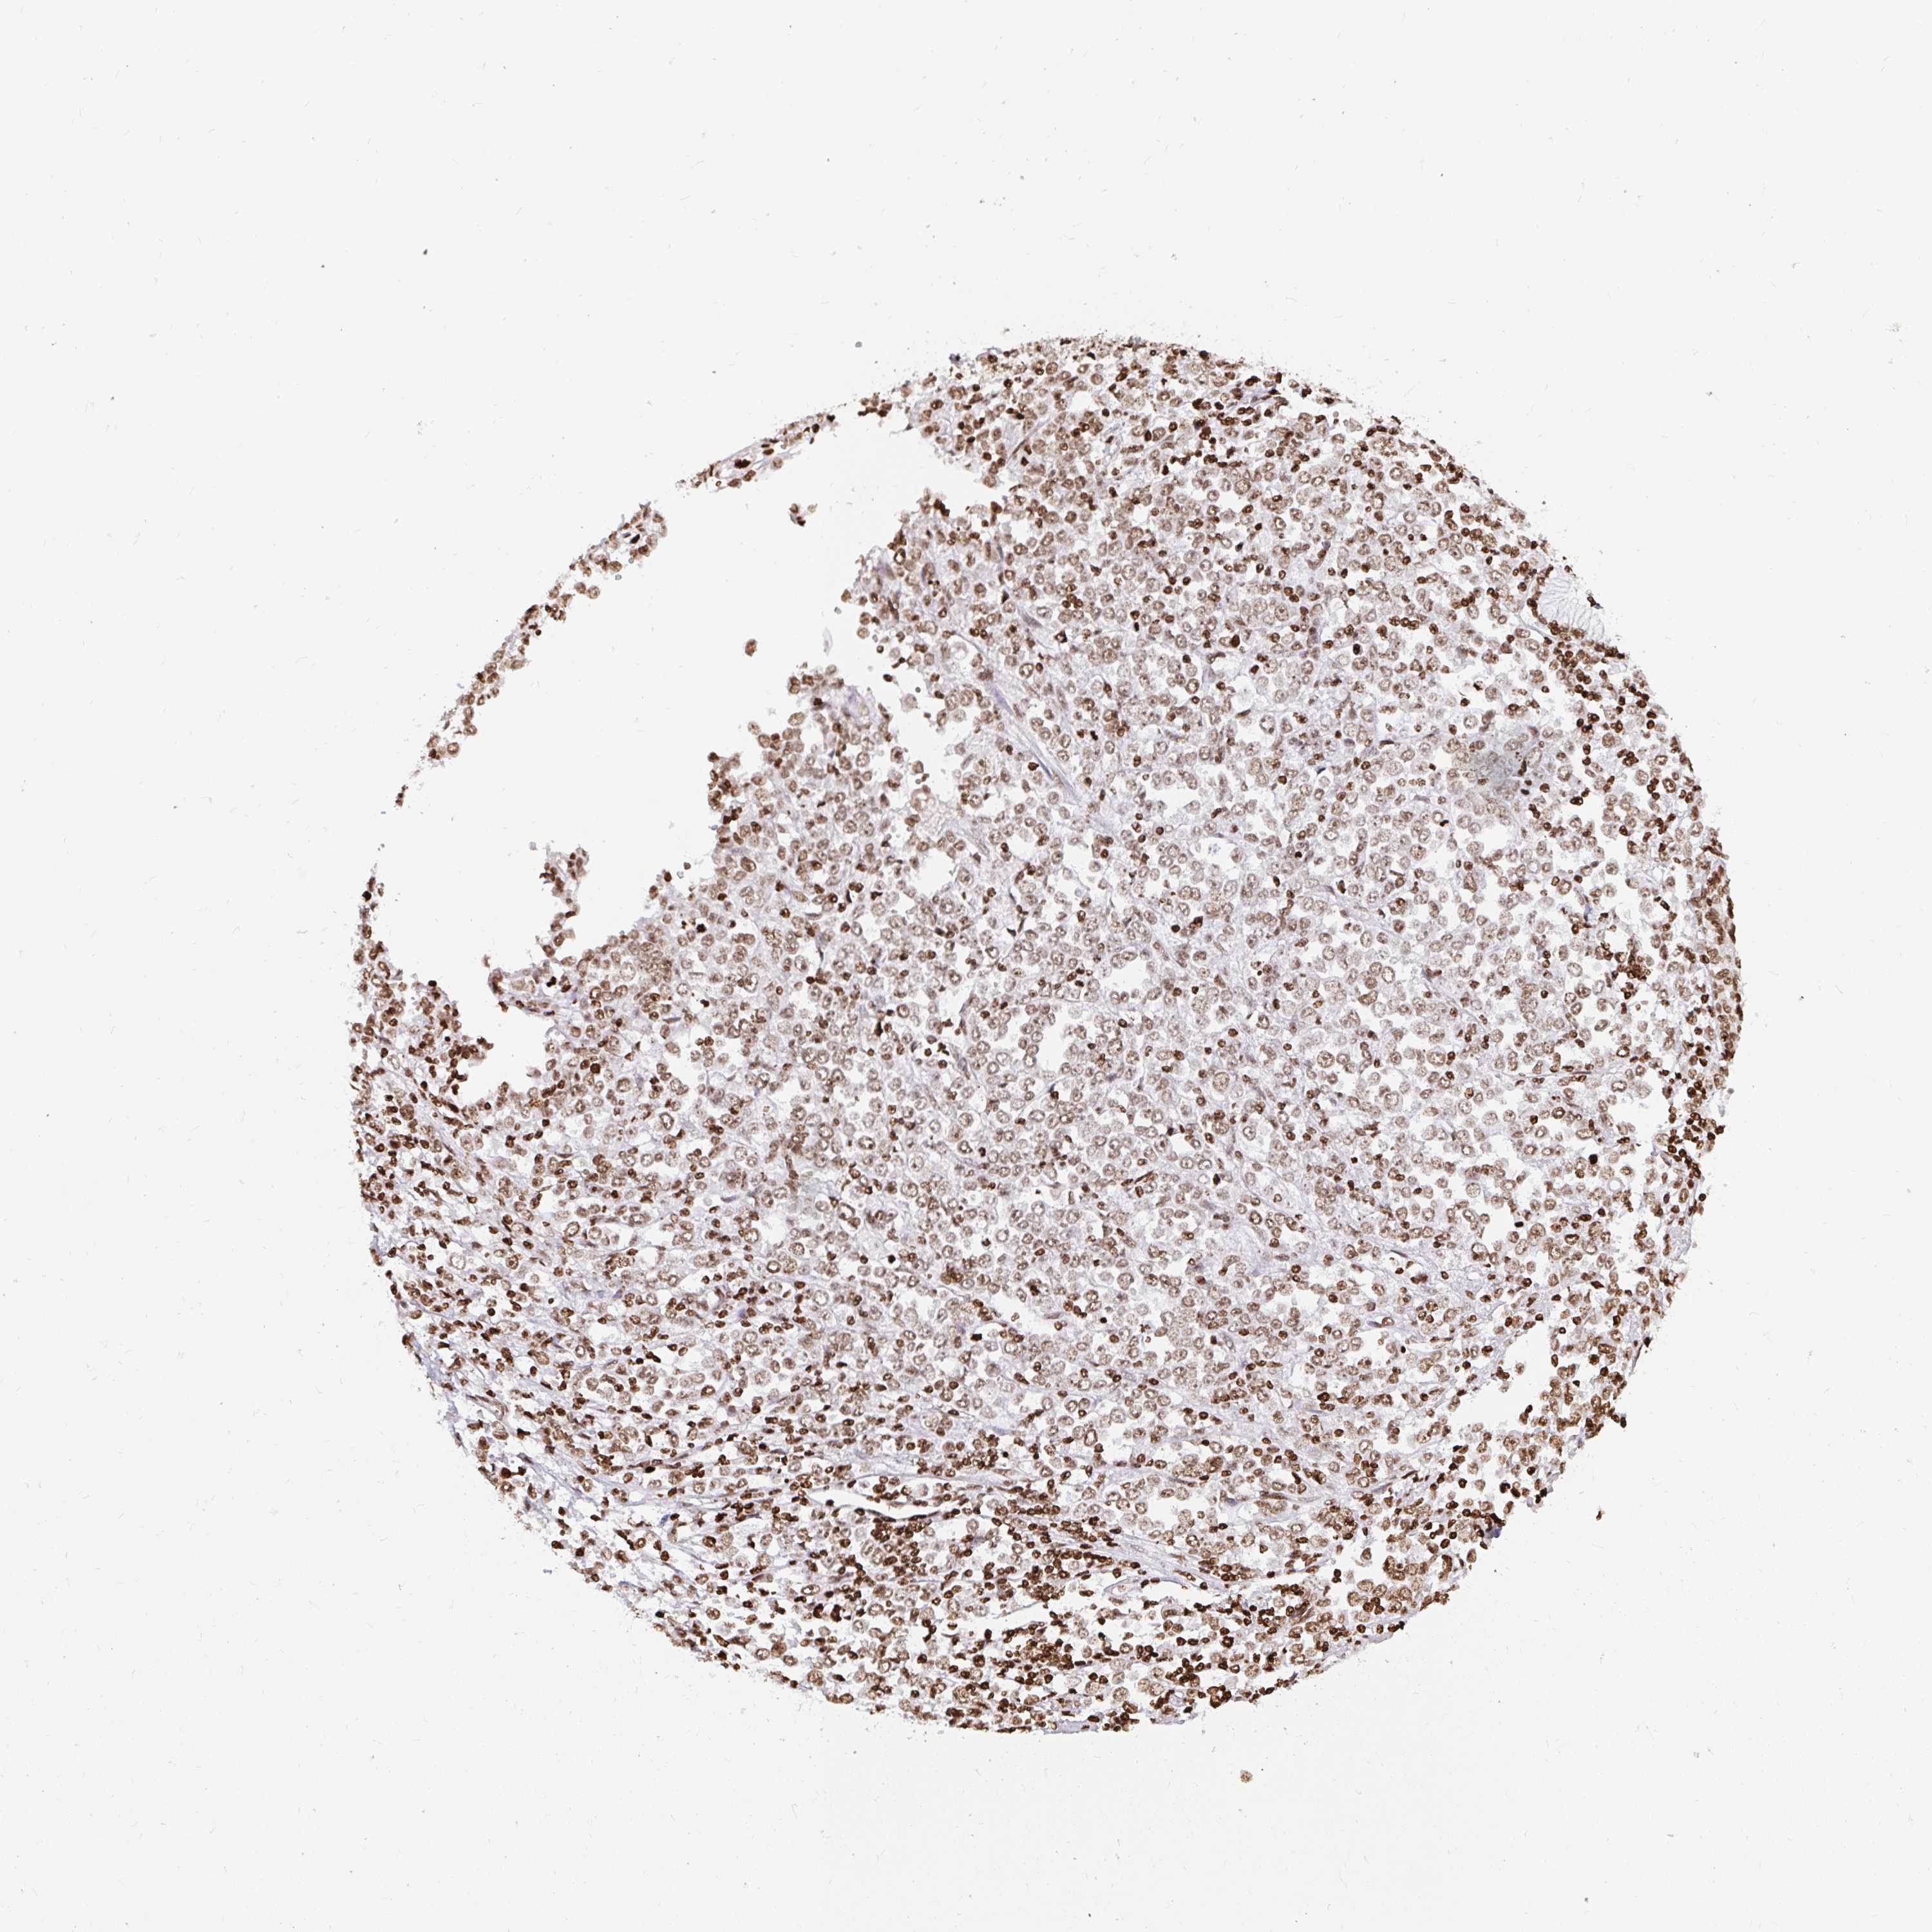

STOMACH CANCER - Protein expressioni

A mouse-over function shows sample information and annotation data. Click on an image to view it in a full screen mode. Samples can be filtered based on level of antibody staining by selecting one or several of the following categories: high, medium, low and not detected. The assay and annotation is described here.

Note that samples used for immunohistochemistry by the Human Protein Atlas do not correspond to samples in the TCGA dataset.

Antibody stainingi

Antibody staining in the annotated cell types in the current human tissue is reported as not detected, low, medium, or high, based on conventional immunohistochemistry profiling in selected tissues. This score is based on the combination of the staining intensity and fraction of stained cells.

Each image is clickable and will lead to virtual microscopy that enables deeper exploration of all samples and also displays staining intensity scores, fraction scores and subcellular localization as well as patient and tissue information for each sample.

Antibody CAB062336

Staining

High

Medium

Low

Not detected

Intensity

Strong

Moderate

Weak

Negative

Quantity

>75%

75%-25%

<25%

None

Location

Nuclear

Cytoplasmic/membranous

Cytoplasmic/membranous,nuclear

Adenocarcinoma, NOS